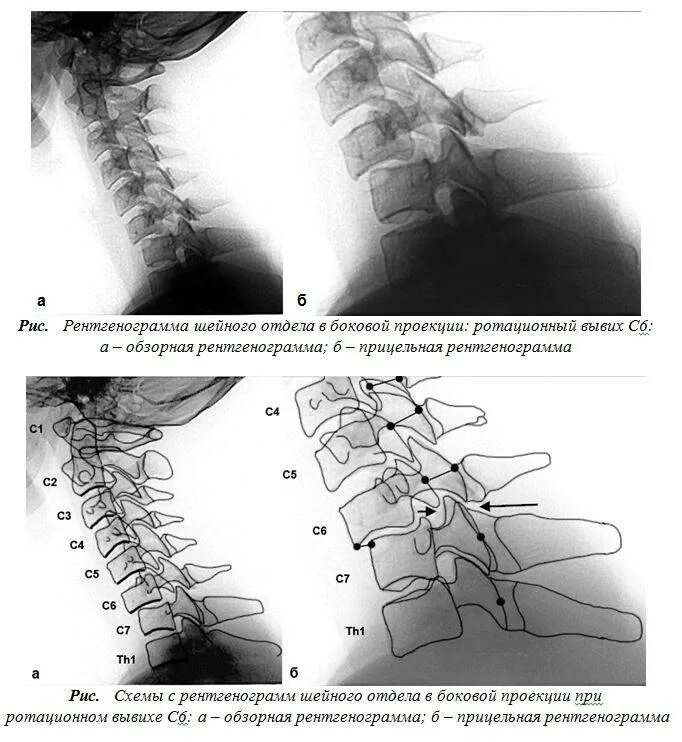

Нестабильность сегмента с3